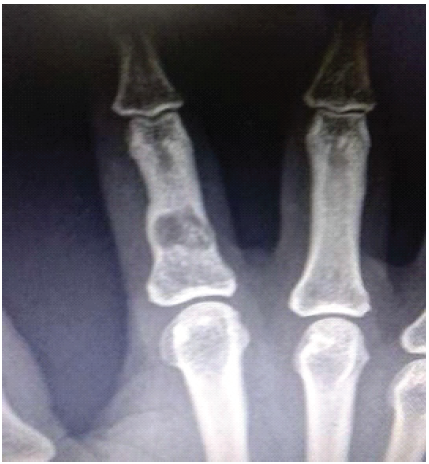

A 41-year-old female patient with a history of falls and complaints of pain in her hand. X-ray showed a lesion on the index finger, which healed after parathyroidectomy (Fig. 4).

Figure 4: A 41-year-old female patient with a history of falls and complaints of pain in her hand. X-ray showed a lesion on the index finger, which healed after parathyroidectomy.